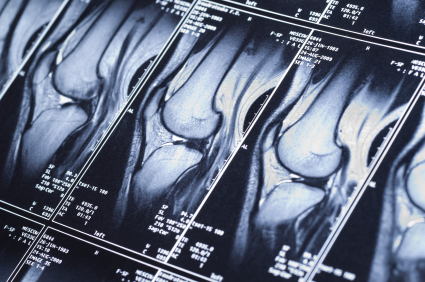

The Clinic

Treatments